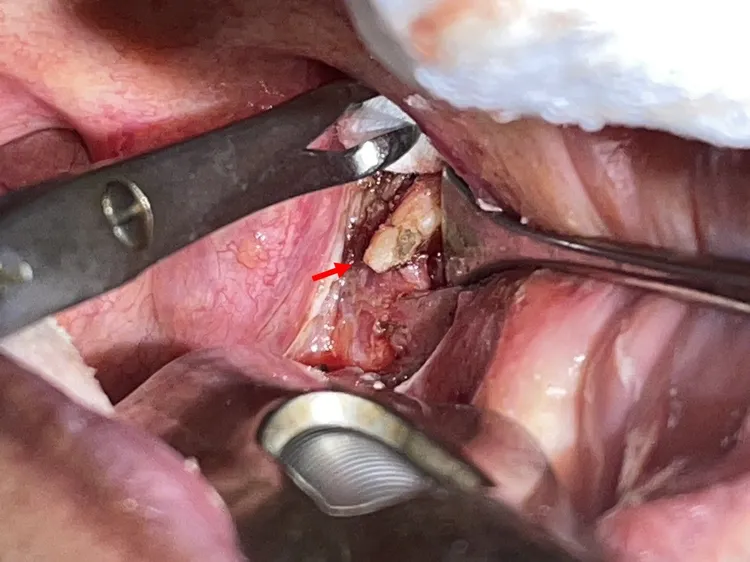

男子扁桃腺後方的扁桃窩,出現不該有莖突(箭頭),這根骨頭讓男子喉嚨老是卡卡的,吞嚥不順。侯思任醫師提供

手術時,侯思任摘除掉男子左側扁桃腺、翻開肌肉,發現男子扁桃腺後方的扁桃窩,有根白白的骨頭,其實這是位在耳道下方的莖突,這根骨頭因鈣化等因素往前傾或長度太長,長到扁桃腺後方,「這一帶有很多神經血管,一旦(有骨頭)壓迫,就可能出現喉嚨痛或卡卡、轉脖子痛、頭痛、耳朵痛等不適。」

這根骨頭讓男子喉嚨老是卡卡的,吞嚥不順。侯思任醫師提供